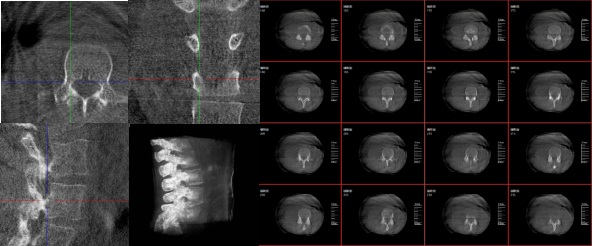

三維重建技術影像